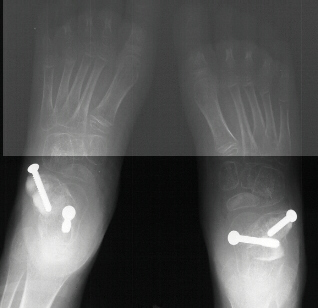

Postoperative X-rays:

- Left Talocalcaneal angle is 24 degrees, Talonavicular angle is 2 degrees

- Right Talocalcaneal angle is 28 degrees, Talonavicular angle is 2 degrees